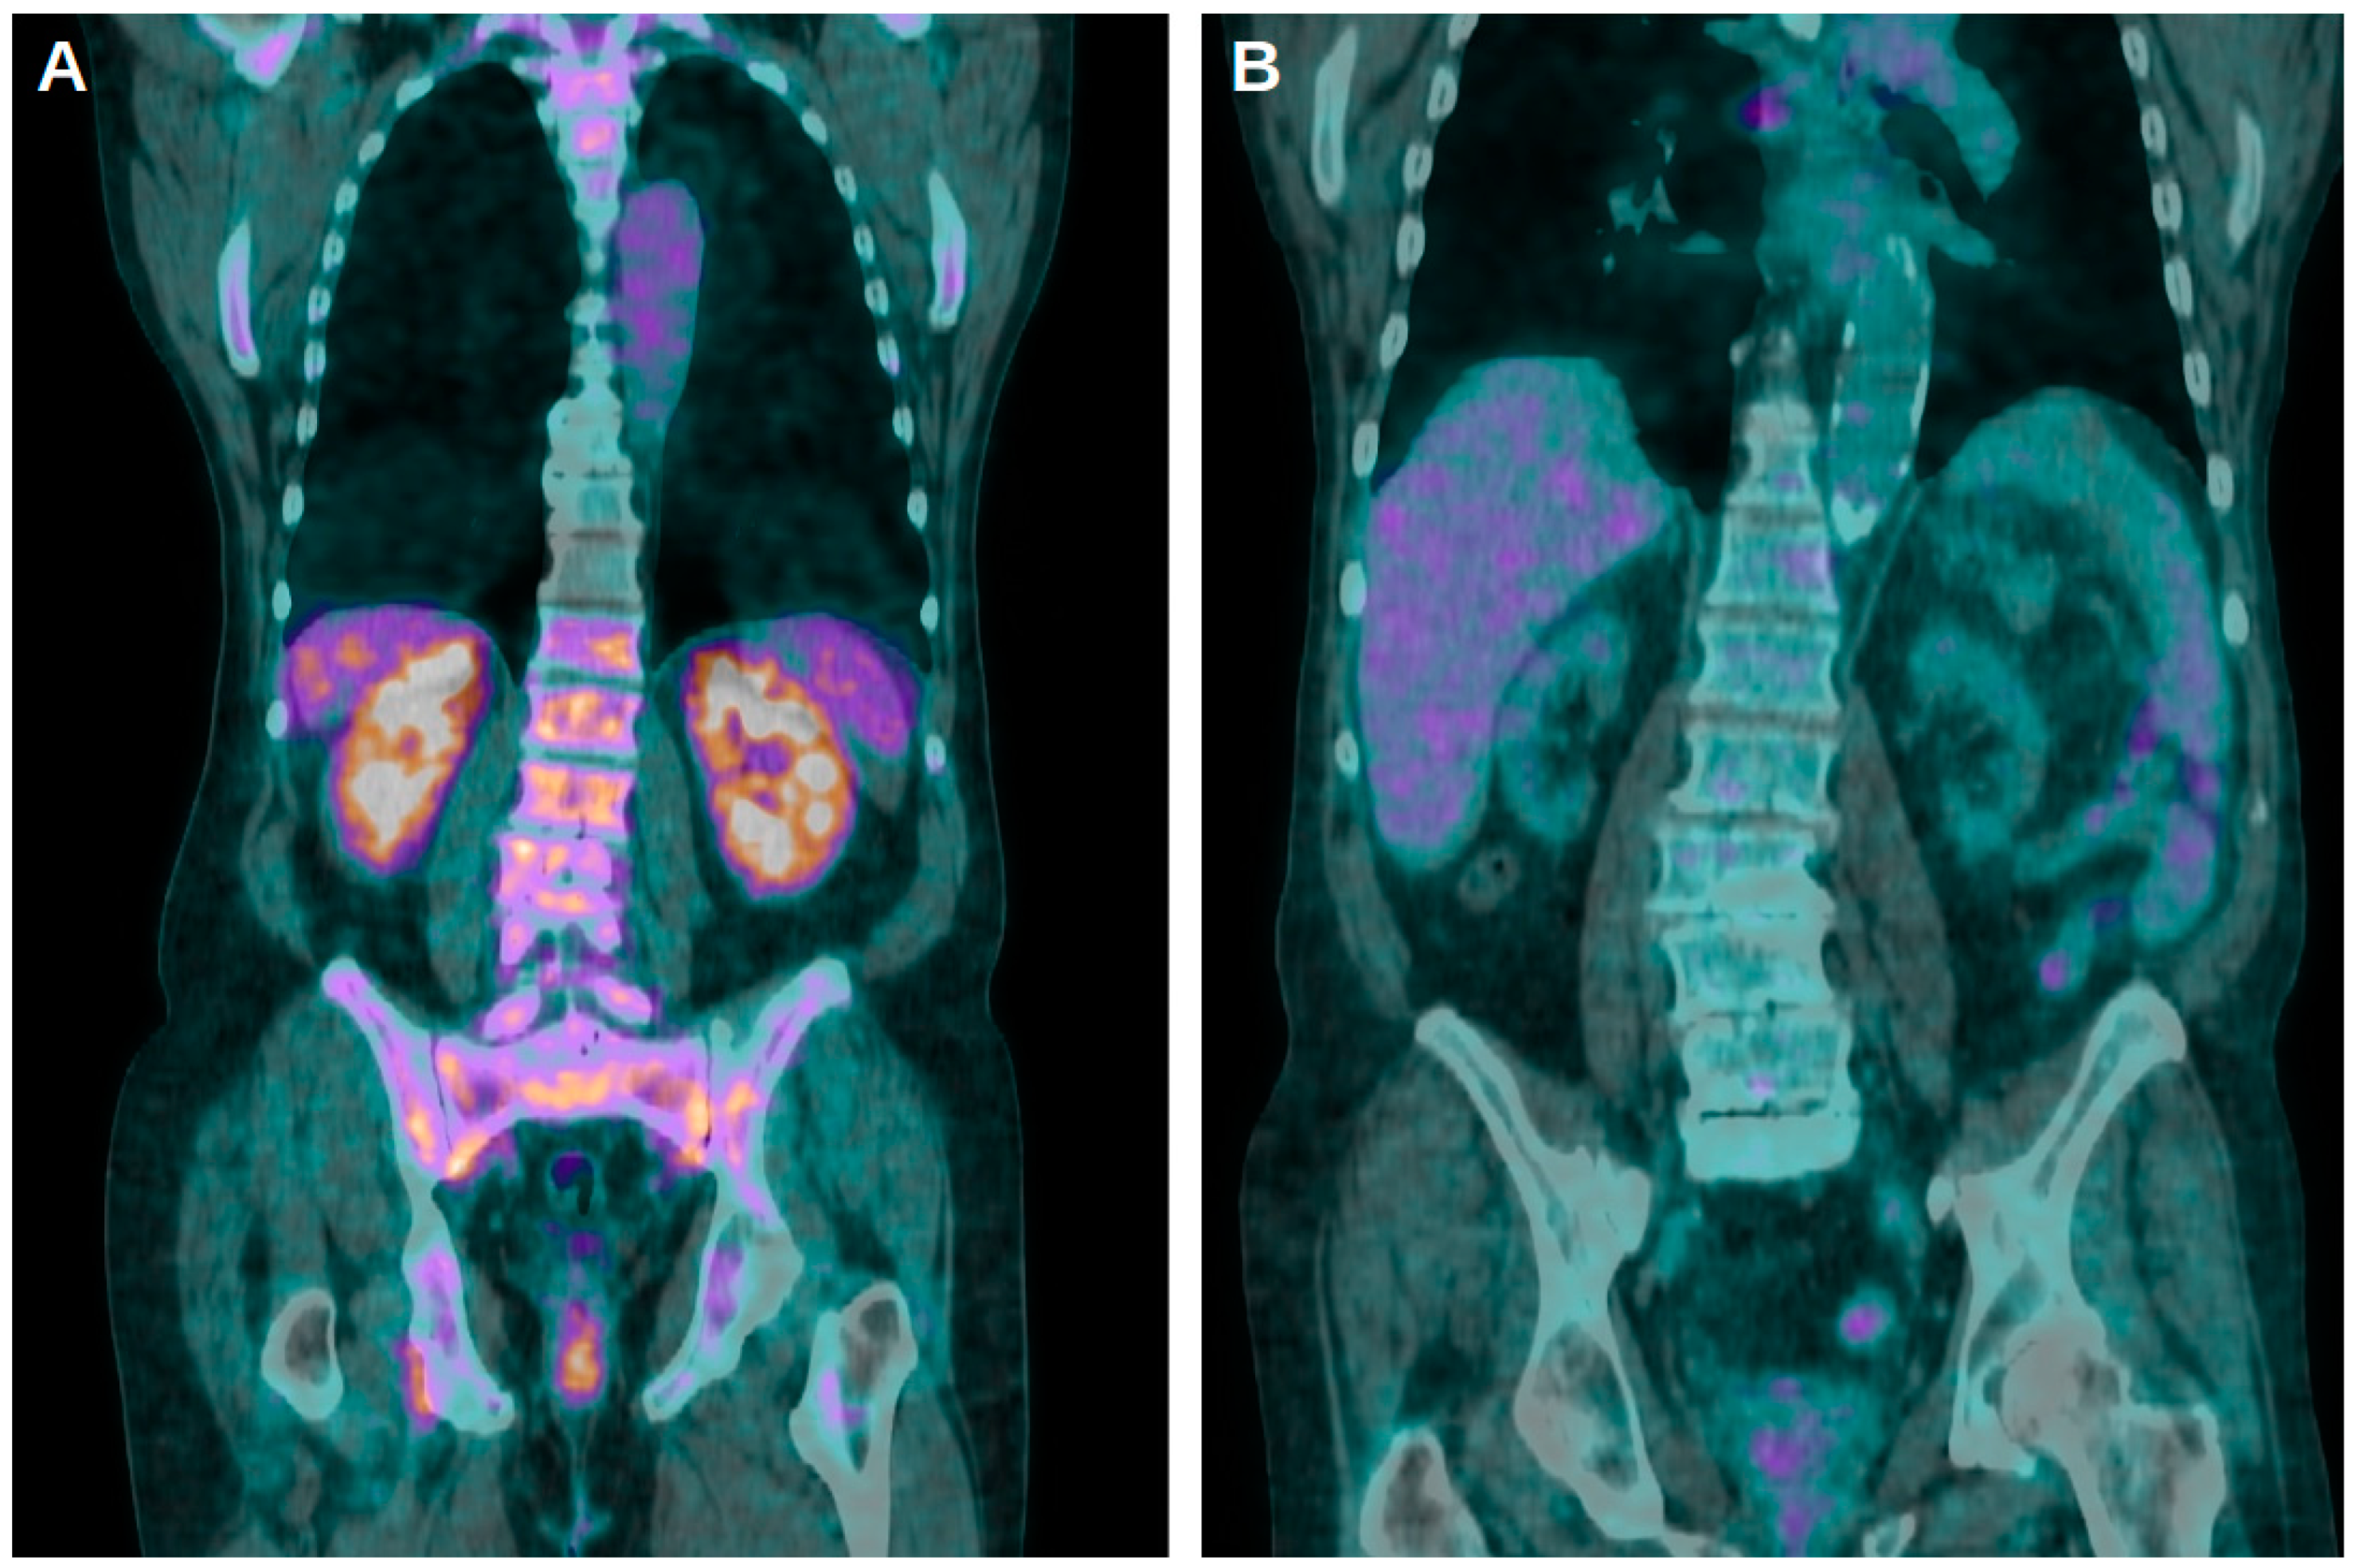

- Pijl, J.P.; Glaudemans, A.W.J.M.; Slart, R.H.J.A.; Kwee, T.C. 18F-FDG PET/CT in Autosomal Dominant Polycystic Kidney Disease Patients with Suspected Cyst Infection. J. Nucl. Med. 2018, 59, 1734–1741. [Google Scholar] [CrossRef] [PubMed]